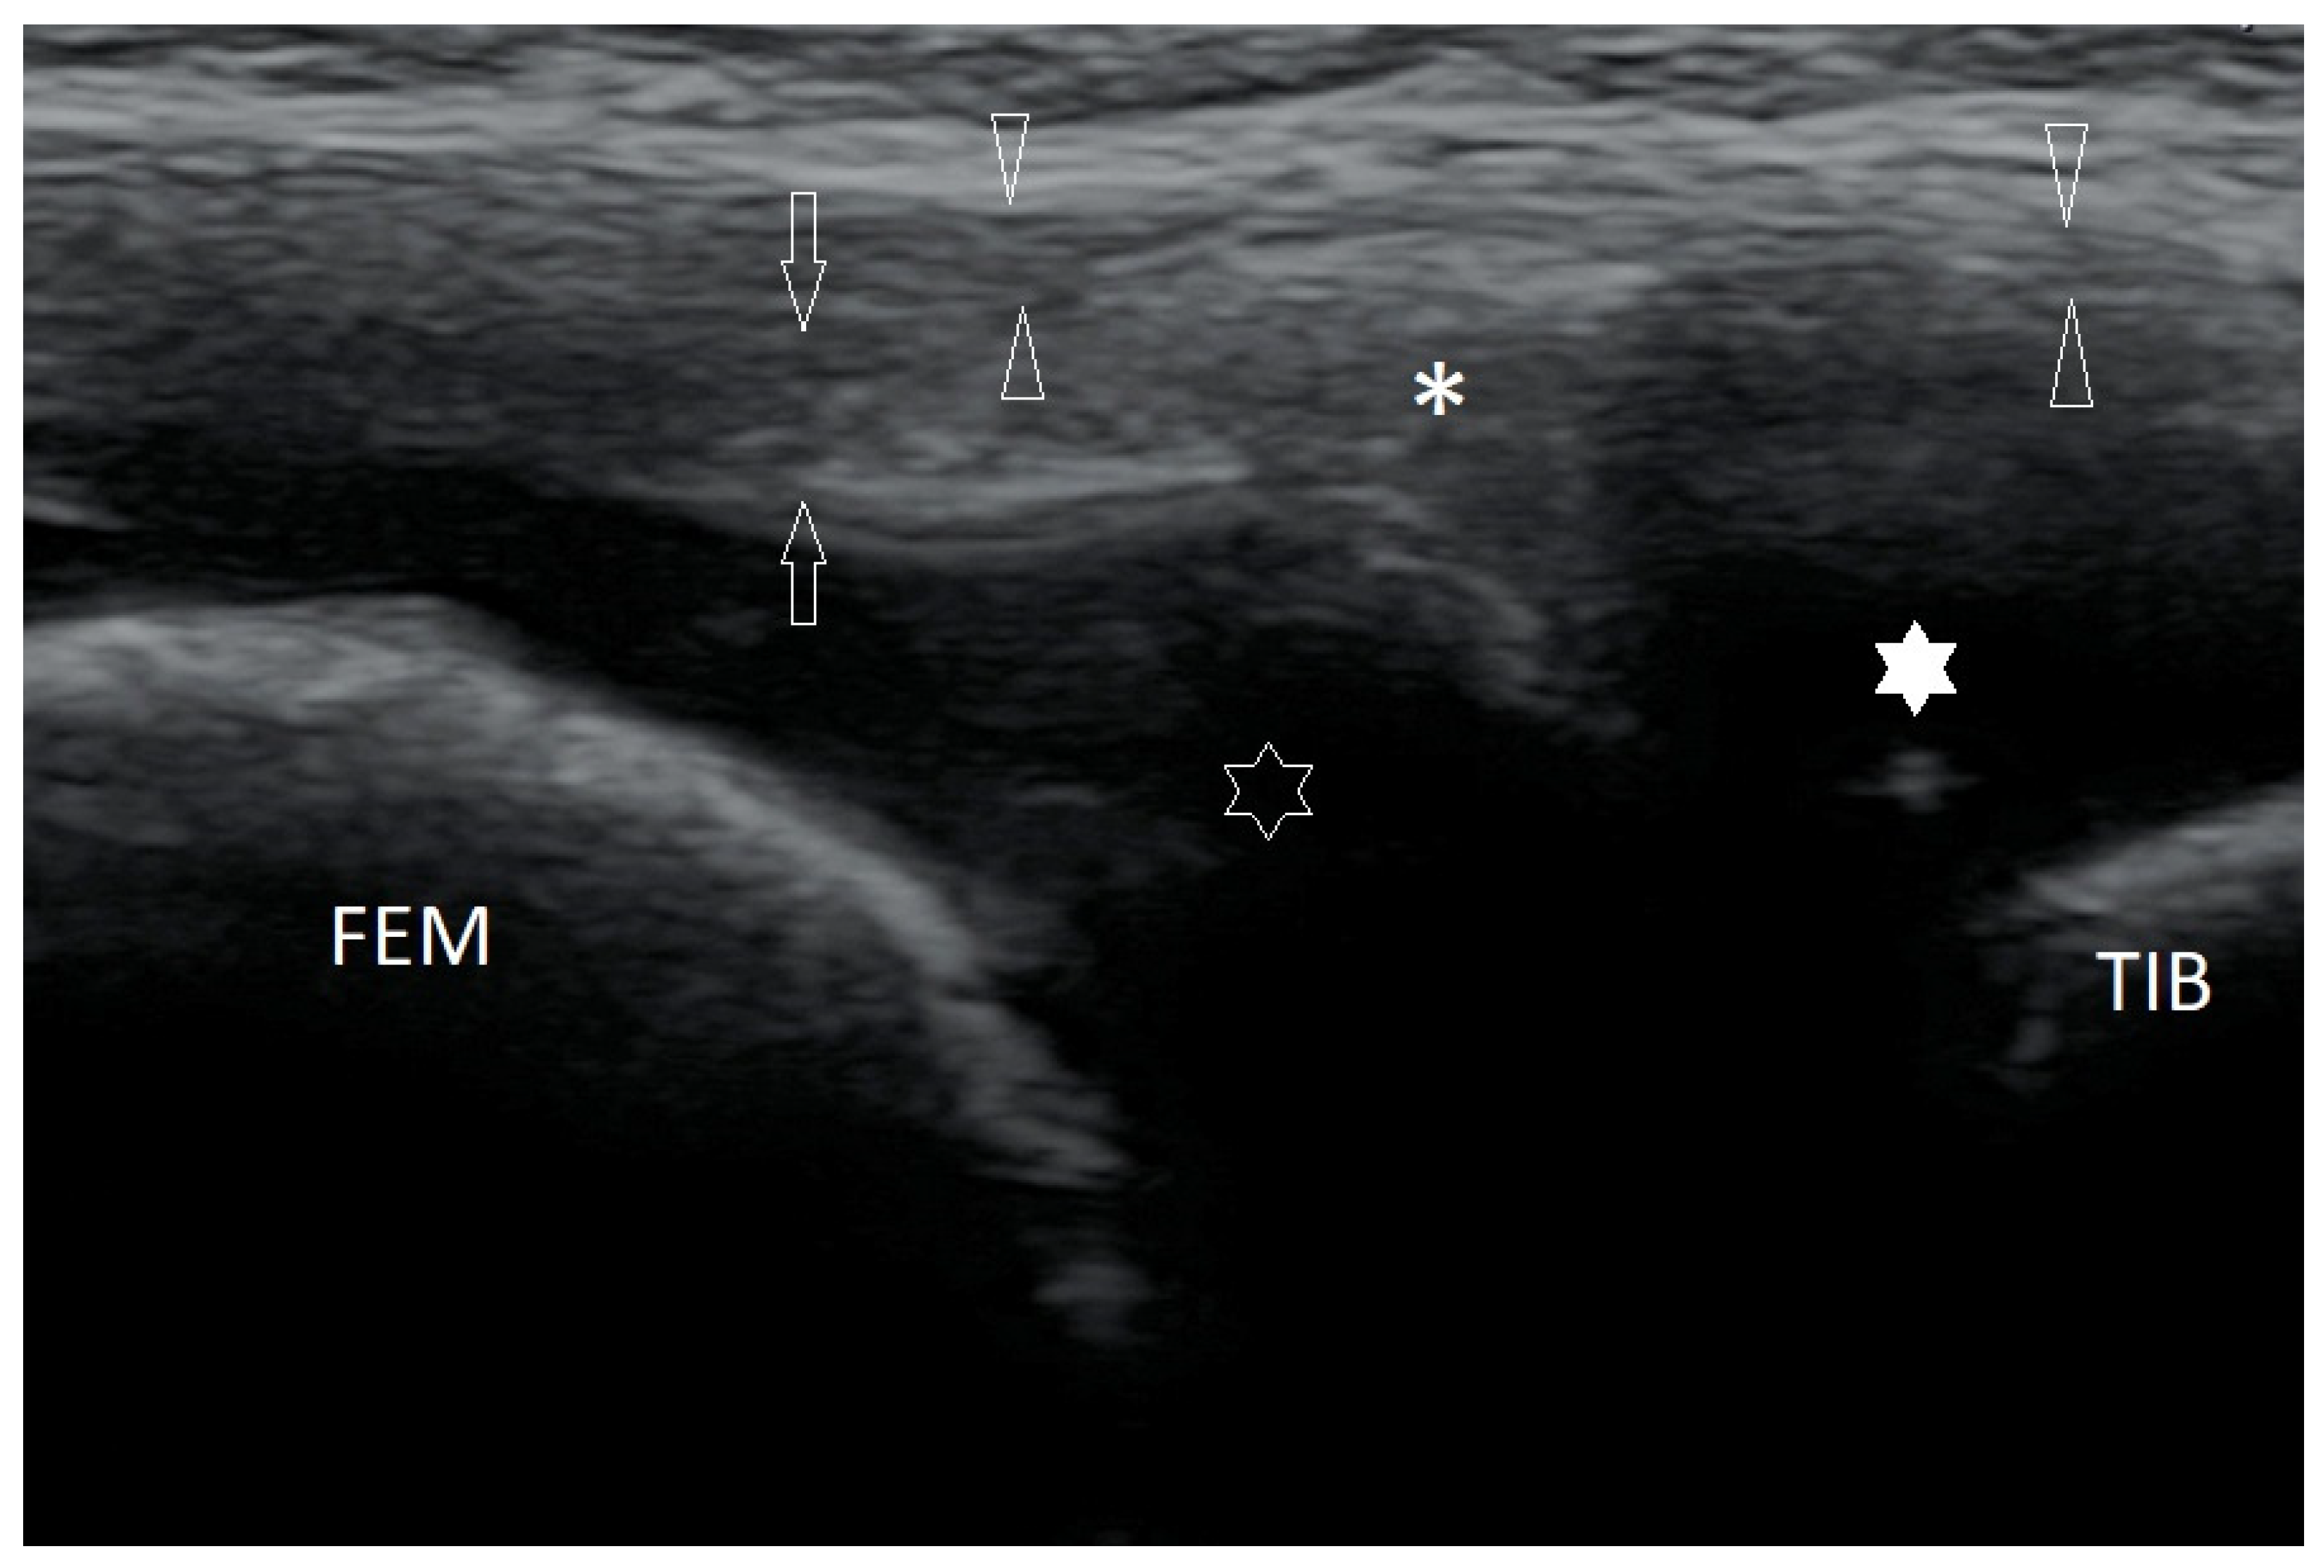

3.2.1. Osteochondritis Dissecans

3.2.7. Baker’s Cysts